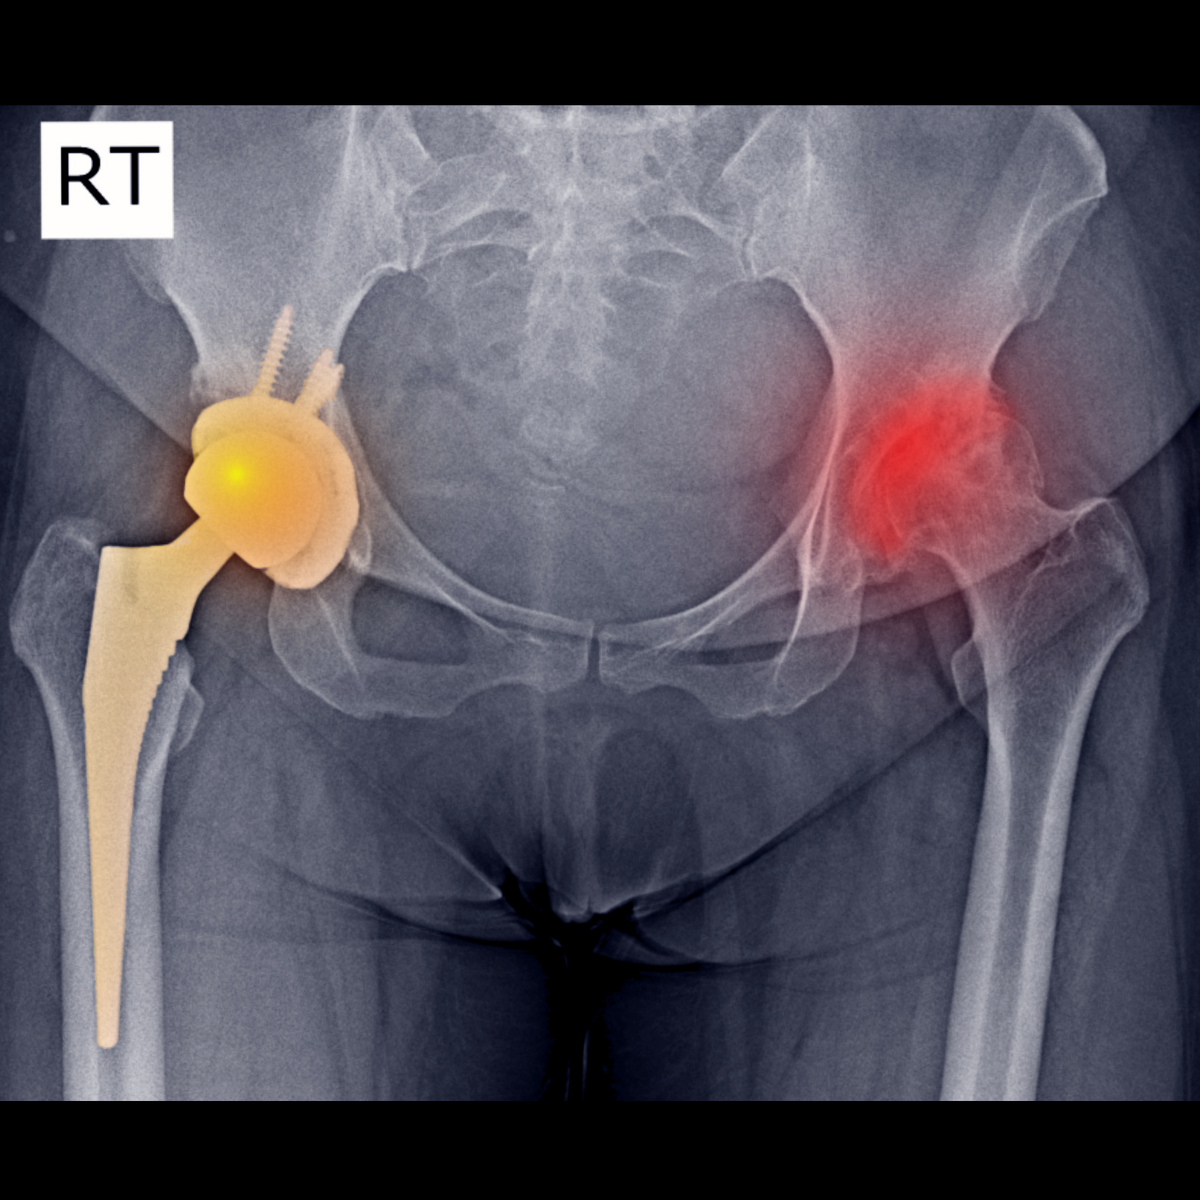

Dislocation of the hip joint is classified into two types. Simple one where there is dislocation of hip, but no fracture is seen, and complex one which is characterized by dislocation along with fracture of acetabulum and femur. Pain in the hip region is the predominant feature seen. Along with this, complete restriction of movement occurs. It can be noticed that the patient is unable to walk. Difficulty in movement or complete immobility often marked with tenderness and swelling is seen. Pain in hip can radiate to the lower leg and back. The patient may also complain of numbness and tingling in the legs in cases of neurovascular damage. Hip dislocations may lead to complications like a nerve injury, arthritis, osteonecrosis, etc.

Diagnosis is done on the basis of the symptoms narrated by the patient and the physical examination carried out by the orthopedic doctor. X- ray of the hip joint is the diagnostic investigation. MRI or CT scan can be done to know the extent of injury and involvement of the surrounding structures.